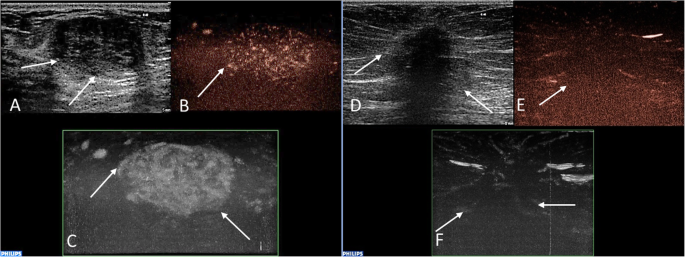

Recorded video loops were processed with Qlab® Quantification software (Philips). Both qualitative and quantitative analysis were employed for evaluation of blood perfusion of the lesions. The MicroVascular Imaging (MVI) software was used to assess the qualitative characteristics of lesions, an example of this method is shown in Fig. 1. The type of vascularization (peripheral or central), the perfusion homogeneity (homogenous vs. heterogenous) and the enhancement degree of lesions compared to the surrounding tissue (poor or absent vs. intermediate vs. rich) were assessed. For quantitative analysis, ROI was placed in the recorded video in the target area in order to analyze the changes in blood flow over time. Two square ROI of standard size 5 mm2 were drawn. The first ROI was placed in the target area of the highest enhancement of a lesion, the second, comparative, ROI was inserted into the surrounding breast tissue at least 1 cm away from a lesion. In the case of a large lesion, when the second ROI could not be placed in the same video loop, additional examination was performed in the same quadrant of the breast outside the observed lesion. The time-intensity curves (TI curves) generated from perfusion data (Fig. 2) were analyzed with a pre-defined software function gamma variate, fitting the saturation curve, which produced all required parameters of quantitative analysis in a short timeframe. These parameters were TTP (time to peak, s.), PI (peak intensity, dB), WIS (wash in slope, dB/s), AUC (area under curve, dB x s). Predefined motion compensation and background set were also applied to obtain these parameters. Motion compensation is an automatic function which detects slight movements in concordance with movements of ROI and eliminates their influence. The background set eliminates the effect of the initial non-zero setting of Time Gain Compensation before contrast administration and thereby eliminates false increase of absolute perfusion intensity. Thus, only the gain of the signal after the application of contrast agent is evaluated. Application examples are given in Fig. 3.

Examples of the evaluation of lesions´ vascularity using the MVI technique. Histopathologically verified fibroadenoma in a 37-year-old female patient (a, b, c). There is a well-circumscribed hypoechoic mass (a) with heterogenous internal enhancement (b) and with rich vascularization compared to the surrounding tissue (c). Verified invasive carcinoma of no special type (NST) in a 79-year-old female patient (d, e, f). Greyscale ultrasound shows poorly defined hypoechoic mass (d). A post-processed CEUS image using MVI application displays peripheral penetrating vessels (e) and heterogeneous internal perfusion of the malignant tumor (f). Abbreviations: MVI, MicroVascular Imaging; NST, invasive carcinoma of no special type; CEUS, contrast-enhanced ultrasound